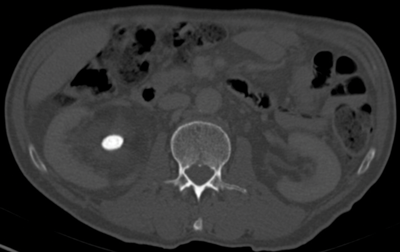

The stone alongside the stent may be masked using abdominal windows, but when changed to bone windows, the stone can be clearly seen due to the difference in HU of the stone compared with the stent (Figure 1) [1].

Figure 1a: Abdominal windows stone and stent.

Figure 1b: Bone windows stone and stent.

This allows a stent or nephrostomy tube to be distinguished from a calculus [2] and can help aid further patient management.